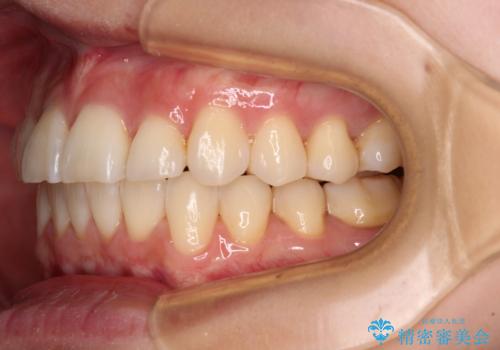

- 奥歯の咬み合わせと、上下前歯の隙間を気にして来院された患者様です。

上顎の歯列全体が、下顎歯列に対して前方に位置しており、その影響で上顎前歯がやや前方に突出している状態でした。

横顔の印象から、抜歯をして積極的に口元を引っ込める必要はなかったため、アンカースクリューを用いて上顎歯列全体を後方に移動させることとしました。

奥歯の咬み合わせは理想的な状態に改善され、その結果として上下歯列もバランスの良い位置に収めることができました。

若干ではあるものの上顎前歯を内側に移動させることができ、以前よりも口が閉じやすいと感じるようになりました。